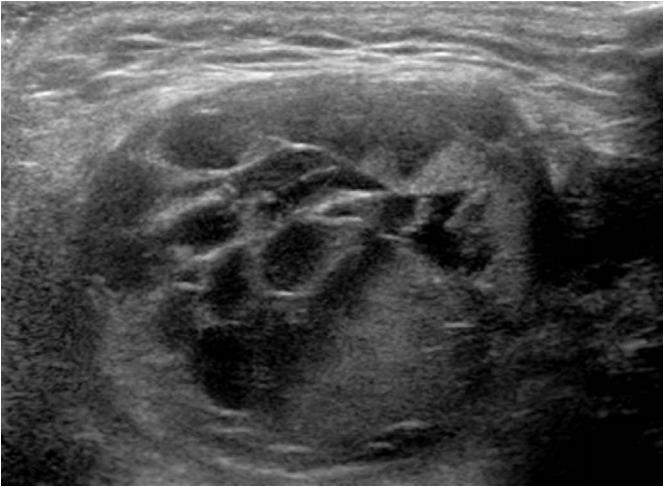

Groin lesions can be classified as neoplastic or non-neoplastic. Neoplastic lesions include lipoma, epidermoid cyst, angiomyofibroblastoma-like tumor, liposarcoma, and synovial sarcoma, as well as metastases from lymphoma, neuroendocrine carcinoma, and carcinomas of the lung, breast, urinary bladder, ovary, vulva, and colon. Non-neoplastic lesions include hernias, round ligament varices, endometriosis, Kimura disease, Castleman disease, hematoma, and inflammation. Because the clinical implications and therapeutic strategies for groin lesions vary depending on the cause, the ability to noninvasively differentiate among etiologies is very important. Although there is substantial overlap in ultrasonographic findings across various groin lesions, some ultrasonographic features, along with clinical characteristics, may suggest a specific diagnosis. Familiarity with the ultrasonographic and clinical features of various groin lesions facilitates accurate diagnosis and treatment.

腹股沟病变可分为肿瘤性或非肿瘤性。肿瘤性病变包括脂肪瘤、表皮样囊肿、血管肌纤维母细胞瘤样肿瘤、脂肪肉瘤和滑膜肉瘤,以及淋巴瘤、神经内分泌癌和肺癌、乳腺癌、膀胱癌、卵巢癌、外阴癌及结肠癌的转移瘤。非肿瘤性病变包括疝、圆韧带静脉曲张、子宫内膜异位症、木村病、卡斯特曼病、血肿和炎症。由于腹股沟病变的临床意义和治疗策略因病因不同而异,因此无创鉴别病因的能力非常重要。尽管各种腹股沟病变的超声表现有很大重叠,但一些超声特征结合临床特点可能提示特定诊断。熟悉各种腹股沟病变的超声和临床特征有助于准确诊断和治疗。